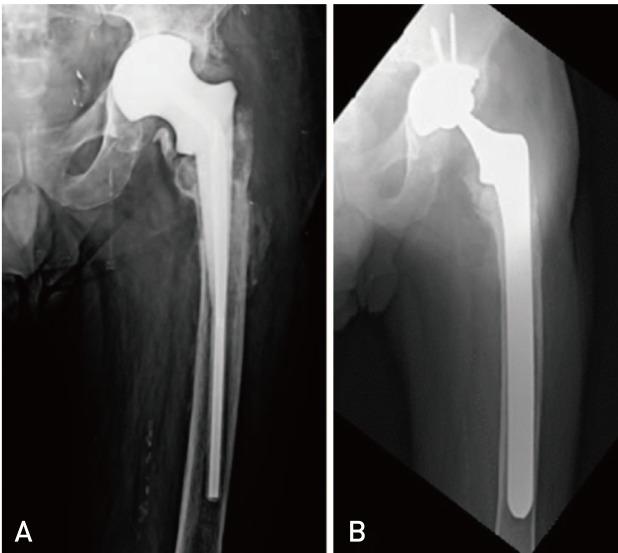

Periprosthetic joint infection (PJI) due to is rare. It frequently occurs patients receiving immunosuppressive medicine. We describe two periprosthetic infection of two immunocompromised patients. Both of patients were receiving azathioprine and prednisolone therapy. First patient presented six years after total hip arthroplasty with a huge abscess on her right thigh that was reached to femoral component through the lytic area of lateral femur. Second patient presented with drainage from his hip and he had undergone two-step revision surgery for PJI 3 months ago. There is no consensus in the treatment of periprosthetic salmonella infections. We prefer two-step revision surgery for these infections as previously described in the literature.